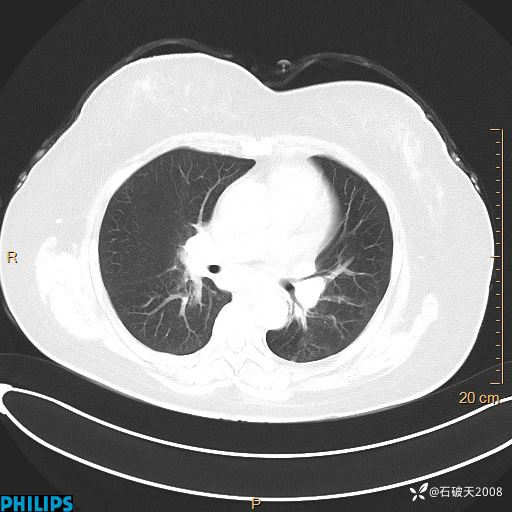

肺结节病?纵膈型肺癌?淋巴瘤?有点意思,欢迎围观

女 52岁 主 诉:咳嗽10余天,咳痰2天。

现病史:10余天前无明显诱因出现咳嗽,呈阵发性干咳,伴咽喉部发痒,无咽痛,无咳痰,无鼻塞、流涕、打喷嚏,无发热、畏寒、寒颤,无头痛、头晕,无胸闷、胸痛,无反酸、烧心,无腹痛、腹泻,无尿频、尿急,无皮疹等,在当地诊所求治,给予口服药物治疗(具体不详),病情无好转。遂在当地社区卫生服务中心开具口服药物治疗(具体不详),疗效欠佳。2天前出现咳痰,在我院门诊求治,行胸部CT提示肺部感染,建议住院,患者要求口服药物治疗,目前仍咳嗽、咳白色粘痰,白天量多,夜间自觉喉部喘鸣音,遂再次来院就诊,以“肺部感染”为诊断收入院。发病以来,神志清,精神可,饮食可,夜间睡眠差,大小便正常,近期体重无明显变化。

纵隔窗